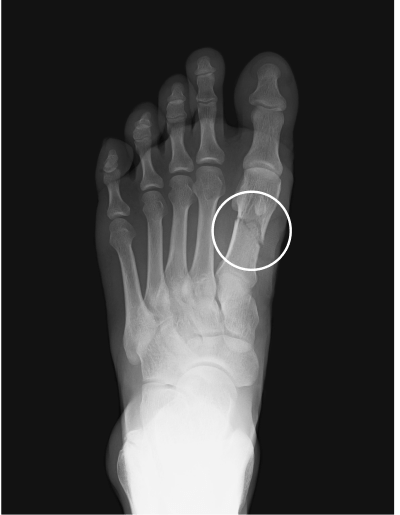

Metatarsal fracture

age 16

Femur fracture

age 13